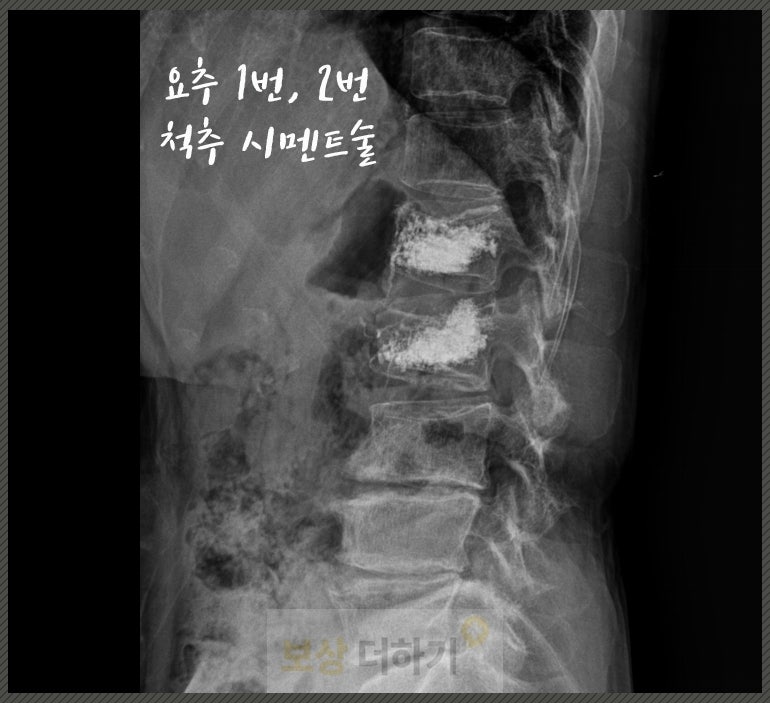

엑스레이 및 MRI 검사를 했고 허리 뼈인 요추 1번, 2번 골절이 진단됐습니다. 정확히 표현하면 압박 골절로, 넘어지실 때 충격을 크게 받으면서 척추체가 찌그러지고 눌린 것입니다.

골다공증 환자 [경피적 척추체 성형술] 골시멘트술 시행 요추 골절은 뼈 안쪽에서 미세하게 계속 무너지고 자극되면서 통증을 유발합니다. 이때 골시멘트를 주입하게 되면 뼈가 안정화되면서 통증이 감소할 수 있죠. 또한 사례자분처럼 골다공증으로 인해 뼈가 약해진 상태에서는 척추체가 계속 찌그러질 위험이 높아요. → 통증 감소, 축가적 붕괴를 막기 위해 경피적 척추체 성형술을 시행 받으셨습니다.